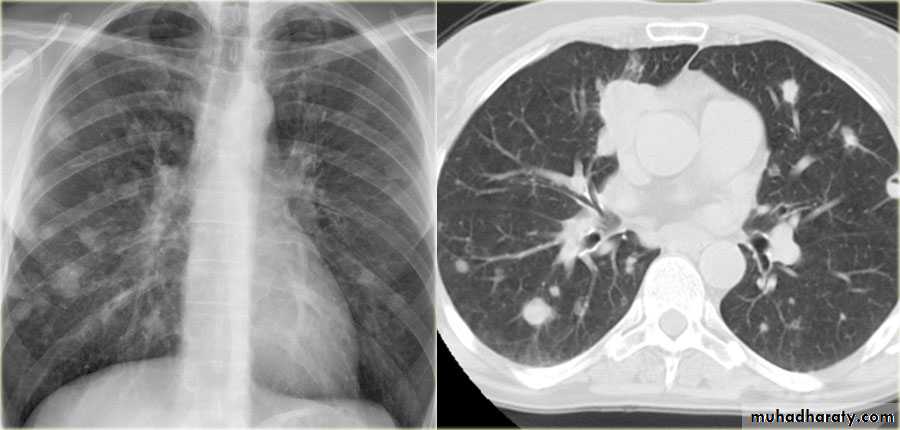

Fall from the 2nd floor